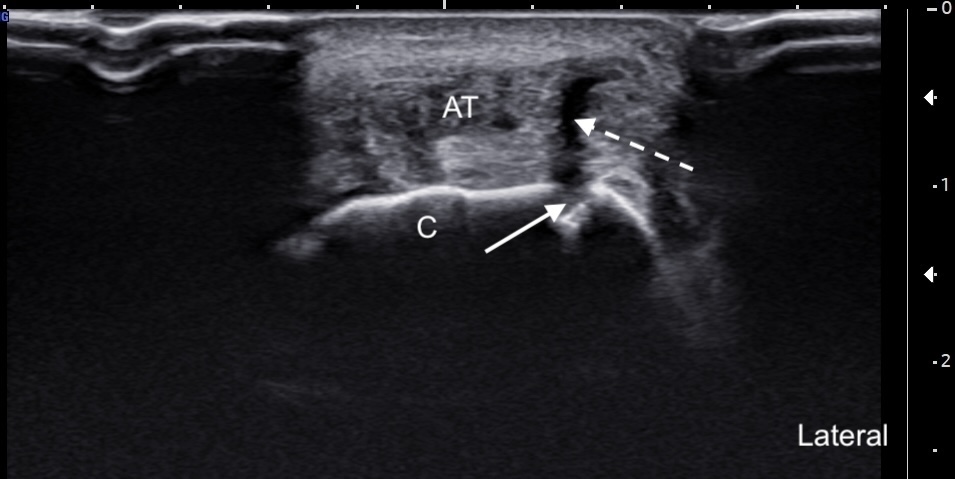

Labeled short-axis ultrasound image of the insertional Achilles tendon, a few millimeters distal to the superior edge of the calcaneus, demonstrating findings similar to those in Figure 4, with the addition of a clearly visible subcortical cyst.

Labels: AT: Achilles tendon, C: calcaneus, solid arrow: subcortical cyst, dashed arrow: partial tear.

Unlabeled short-axis ultrasound image of the insertional Achilles tendon, a few millimeters distal to the superior edge of the calcaneus, demonstrating findings similar to those in Figure 4, with the addition of a clearly visible subcortical cyst.

Labeled short-axis ultrasound image of the insertional Achilles tendon, at the level of the superior edge of the calcaneus showing increased thickness, hypoechogenicity, and partial tearing of the deep tendon fibers.

Labels: AT: Achilles tendon, C: calcaneus, solid arrow: retrocalcaneal bursa, dashed arrow: partial tear.